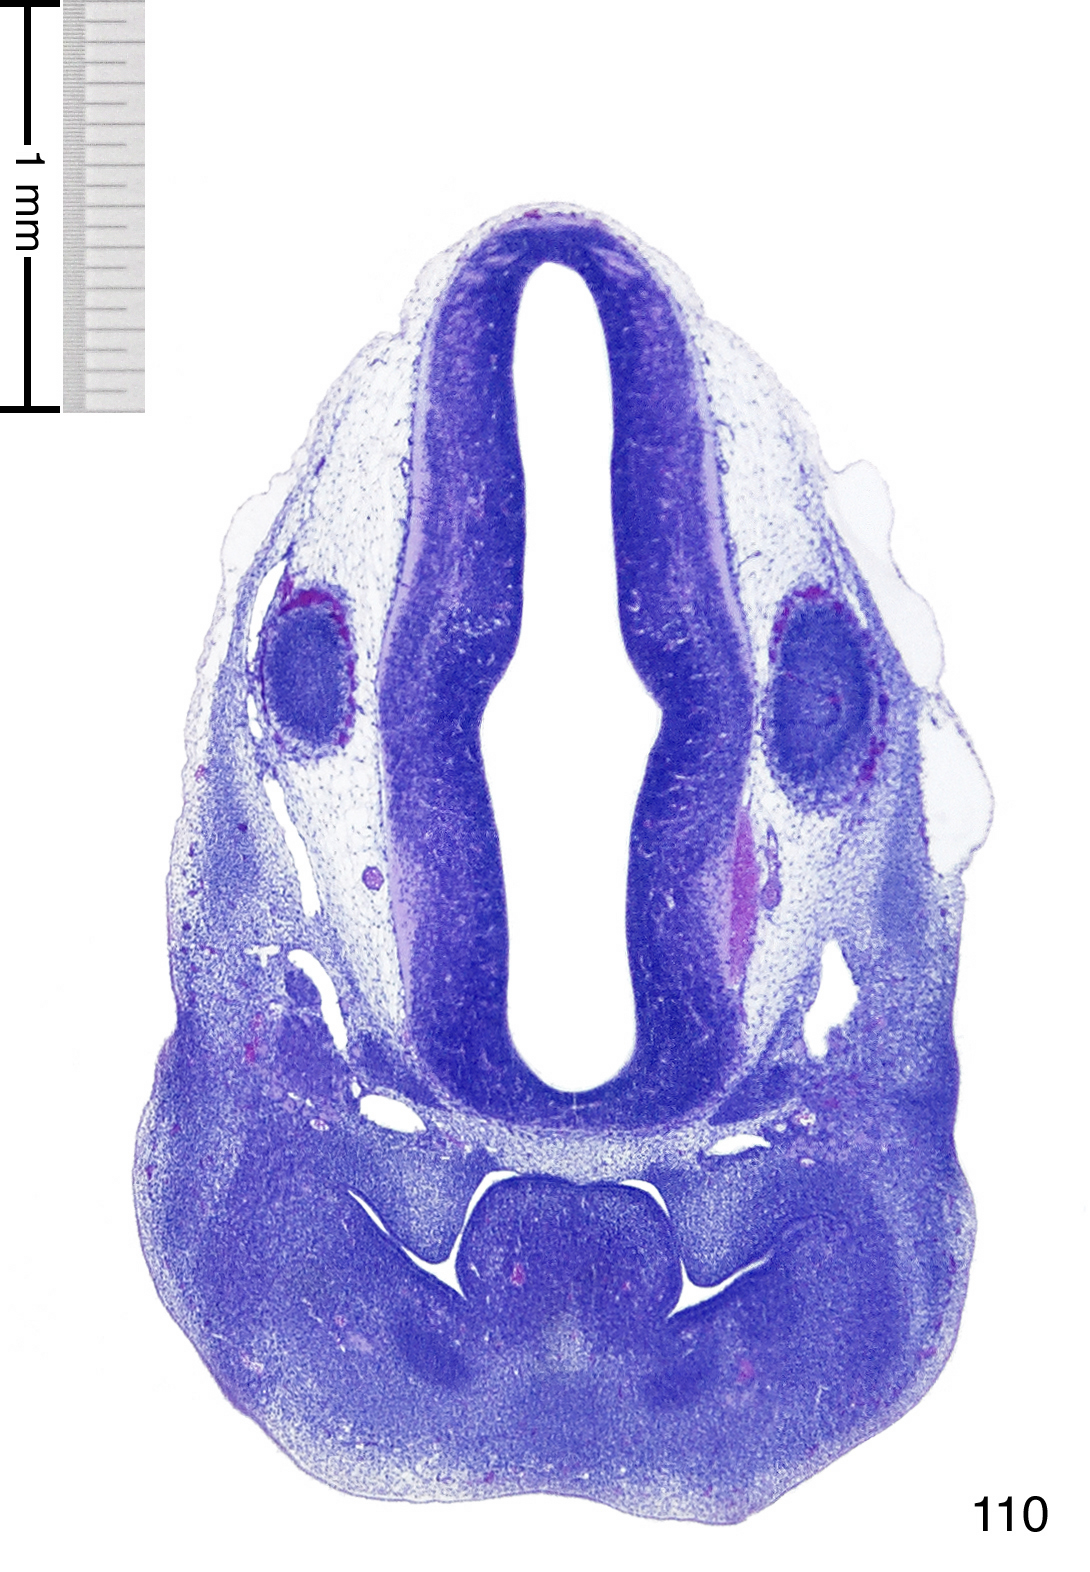

C57BL/6J GD12 Mouse Brain Atlas

Slides from U. Schambra, coronal cuts with slides at every 5th section, with a hematoxylin and eosin (H & E) stain

Currently on section 110.